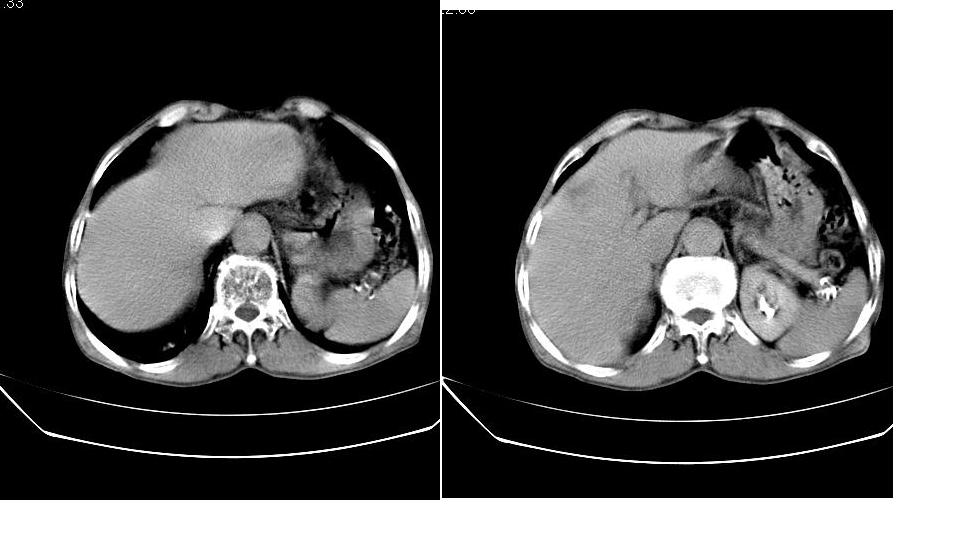

男,76岁,上腹部疼二天来就诊,彩超提示肝左叶占位,随后做上腹部ct平扫,今天做上腹部ct增强扫描,手工推药,效果不好,请谅解。

肝左叶s4肿块强化形式大概是:慢进慢出,逐渐强化----考虑血管瘤/腺瘤?{动脉期应更提前扫}。

肝右叶前段hcc

1)肝右叶前段低密度灶,不排除肝癌可能;建议查afp。2)右肾上极囊肿。

肝内胆管积气扩张,胆囊增大,肝右前叶低密度灶,逐渐强化,一元论,胆系感染,局限性肝脓肿;右肾囊肿。

考虑肝s4段肝脓肿可能?未排除肝癌。右肾上极囊肿。